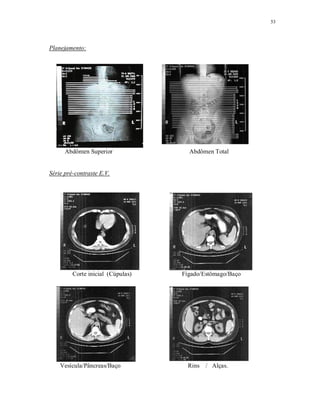

Planejamento:

Abdômen Superior Abdômen Total

Série pré-contraste E.V.

Corte inicial (Cúpulas) Fígado/Estômago/Baço

Vesícula/Pâncreas/Baço Rins / Alças.